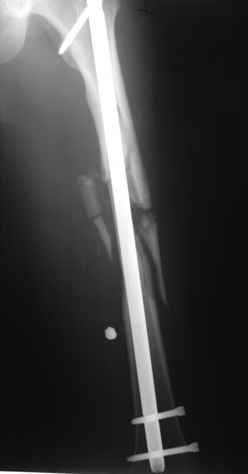

В нашем случае 21 летний боец уличного фронта, фиксацию провели на следующий день, зафиксирован интрамедуллярным штифтом. Не стали делать первичную хирургическую обработку точечной раны, зафиксирован как есть. Клинические снимки:

Конечно, наш случай не эталон, возможно, на месте вам виднее, может быть, нет необходимости ориентироваться на зарубежные ссылки, если получается лечить аппаратом Илизарова на месте, почему нет? Необходимо посмотреть собственный арсенал, чем фиксировать, и какая теория, иначе любой отличный метод можно превратить в источник остеомиелита.

Сам скептически отношусь к тому, когда говорят что одного взгляда достаточно, чтобы сделать такой случай у себя. Без спешки примите решение, возможно, еще не время, и, наверное, будет разумным поехать к тому у кого большой опыт.